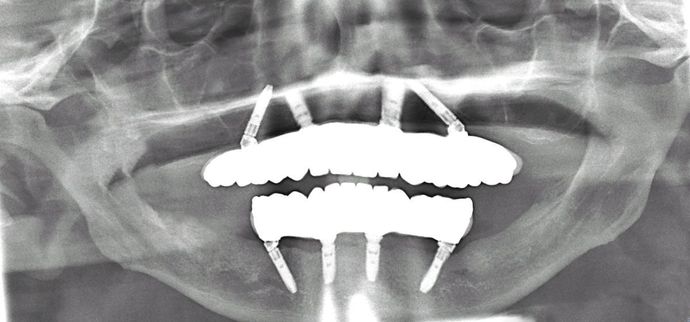

All-on-4/ Full Mouth Dental Implants / Teeth in a Day: Case 6-DG - Upper and lower All-on-4 implant bridges

Procedures : extractions, implants, All on 4 , Teeth in a day, no bone grafting and full mouth reconstruction with monolithic zirconia bridges.